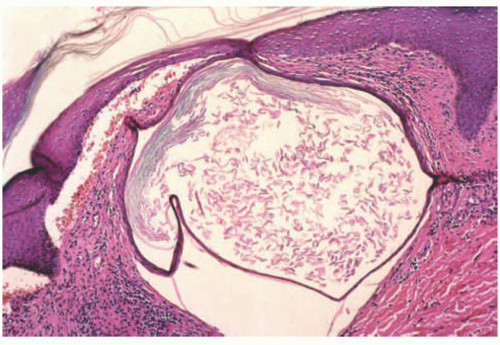

Milia formation is another well-known histopathologic finding associated with DEB. Milia are small dermal cysts lined by squamous epithelium and containing loose keratin (they are essentially miniaturized epidermal inclusion/epidermoid cysts) (Figure 4-17). In one case report, multiple milia was the presenting skin manifestation of DEB.13 However, any disorder that causes repeated skin damage may result in milia formation, making the finding of milia nonspecific (the lesions of EBA, eg, also frequently show milia). Immunomapping studies show the presence of KRT5 and KRT14, laminins, and type IV collagen along the roof of the blister. On ultrastructural examination, anchoring fibrils are often altered or reduced and may even be absent in severe recessive dystrophic forms of EB.